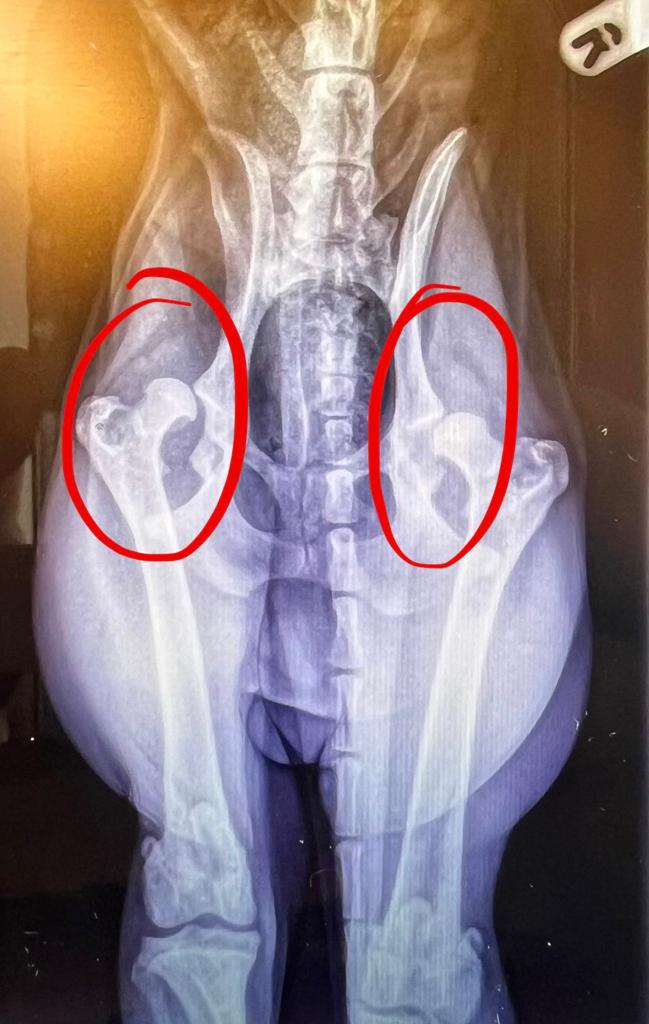

On 12th June 2023, our 9 month puppy was diagnosed with hip dysplasia so severe that his hips are essentially dislocated. To live a normal and pain free life, he'll need two full hip replacements which cost around £7000 each. Without these, we've been advised that his life expectancy will be cut short and his quality of life severely affected, with him likely to develop painful arthritis and even become immobile.

JUDE'S HIPS: